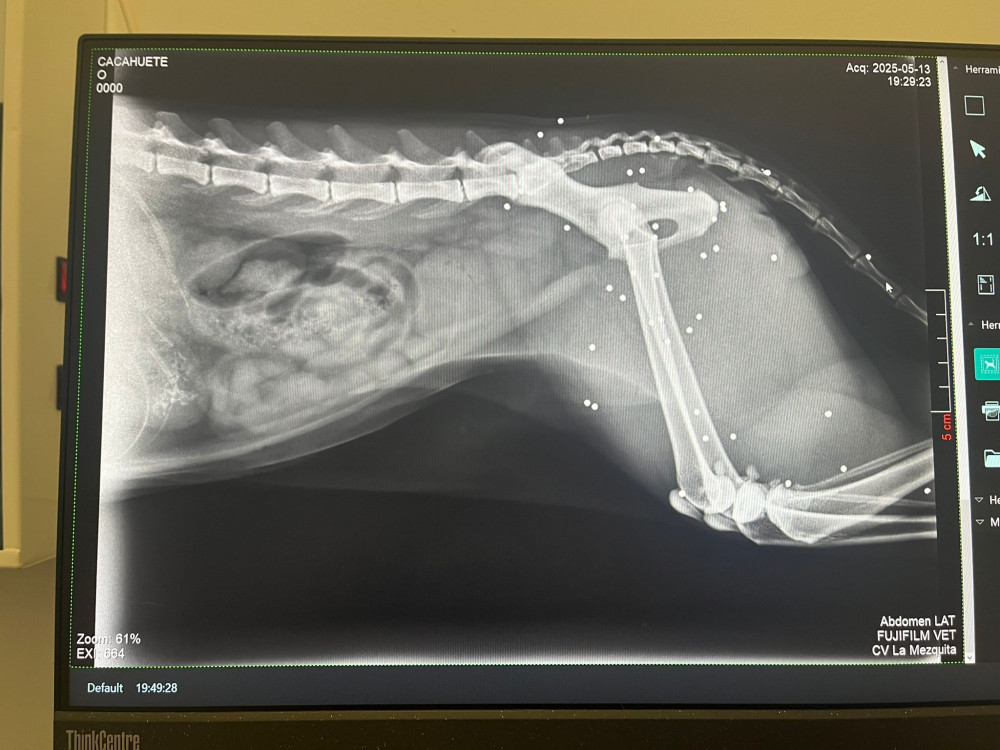

Lo rescatamos desde Francia, y, al llegar aquí, nos encontramos con este panorama desolador para él:  una auténtica barbaridad de perdigones en el cuerpo y una cardiopatía ❤️‍🩹 Las imágenes hablan por sí solas...